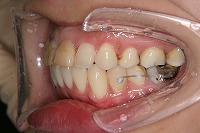

26歳4か月

右